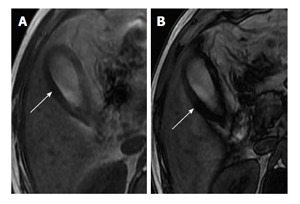

In-phase and opposed-phase chemical shift imaging is helpful in demonstrating fat within the thickened gallbladder wall in patients with XGC[26] (Figure 12). Zhao et al[21] subjected intramural nodules to chemical shift imaging. Seventy-seven point seven percent of XGC nodules showed reduced signal intensity on out-of-phase images. This variable nature of the intramural nodule on magnetic resonance imaging (MRI) can be attributed to the presence of diverse contents like foamy histiocytes, lymphocytes, plasma cells, polymorphonuclear leucocytes, fibrosis, giant cells, microabscess and necrosis within these nodules[22]. The researchers also observed that few nodules (2 out of 11) were detected only on CT and not seen on MRI and attributed this to a lower spatial resolution of MRI. Areas of iso- to slightly high signal intensity on T2-weighted images, showing slight enhancement at early phase and strong enhancement during delayed phase of dynamic study, corresponded with areas of abundant xanthogranulomas[24]. Areas with very high signal intensity on T2-weighted images without enhancement corresponded with necrosis and/or abscesses[24].

Figure 12.

3.0 T magnetic resonance axial chemical shift imaging using in-phase (A) and out-phase sequences (B). Presence of intramural fat is markedly evident in the form of loss of signal from gallbladder wall on out of phase imaging (arrow) compared to in-phase image (arrow).